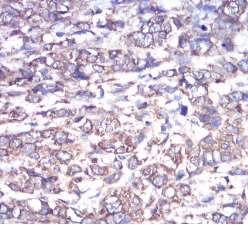

GNAS Mouse Monoclonal antibody[2A2B7]

Immunogen :   Purified recombinant fragment of human GNAS (AA: 42-188) expressed in E. Coli.

IHC    1/200 - 1/1000